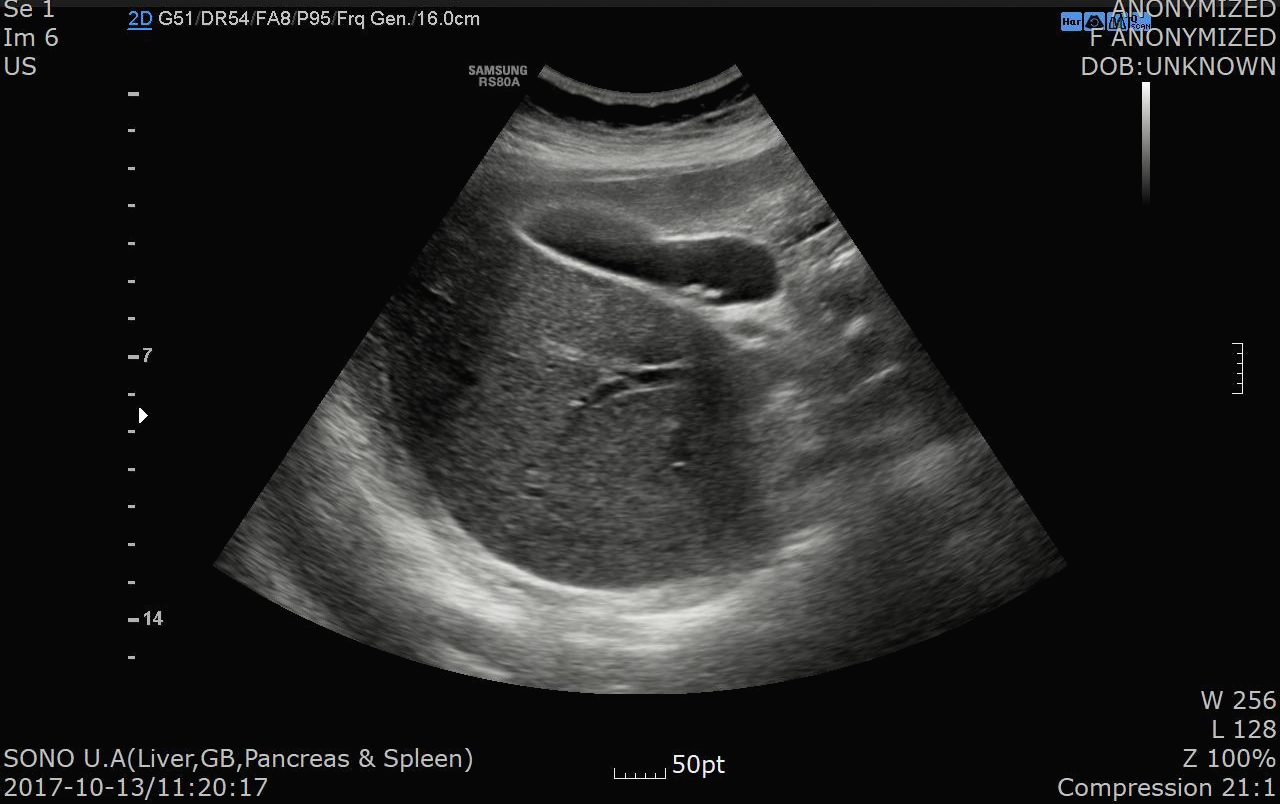

2017.10.13일 복통으로 저희 병원에서 시행한 복부 초음파가 있어서 비교를 해보니 당시 판독 소견은 아래와 같습니다.

복부초음파 판독소견

Two small GB stones (about 5 mm)

- no evidence of cholecystitis

담낭내에 5mm 크기의 담석이 2개 있으면서 담낭염 소견은 명확하지 않다는 소견입니다.